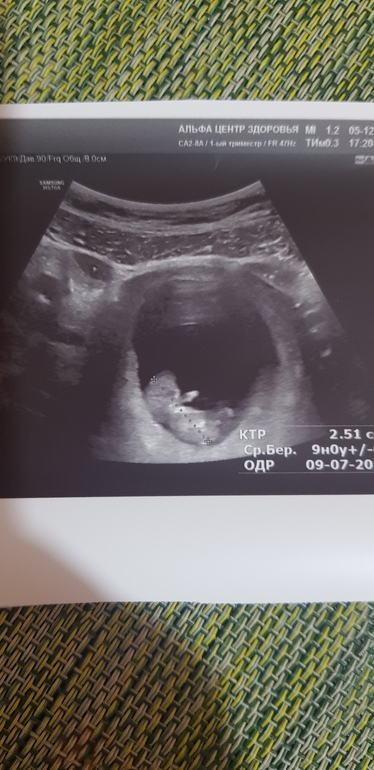

УЗИ, КТГ, доплерИ пошла на узи. Ну не хватает у меня терпения после зб нормально воспринимать коричневую мазню, хоть и предупреждали, что будет после осмотра (из-за эрозии). Малышик наш ручками махал🤗 это не передать, как круто! А всего то 2,5 см! Немножко отстал, то опережал на 2-3 дня , а сейчас по размерам на 4 дня отстает. Сердцебиение ритмичное, но 180 ударов ...Врач узи сказал, что по верхней границе нормы, а гиня что тахикардия! Вот и думай теперь. Я списываю на то, что сама два дня на нервах и даже отдышаться не успела (по лестнице бежала) легла на узи. Есть небольшая гематома 35*3,8 мм. И тонус высотой 10 мм....Блин, до нервничалась🤷♀️ Назначила мне гиня утрожестан и магний. Сказала, что мажет из-за эрозии. В общем, успокаиваюсь и жду 12 недель🙏

Ну и собственно вот он герой, машущий ручонкой😊